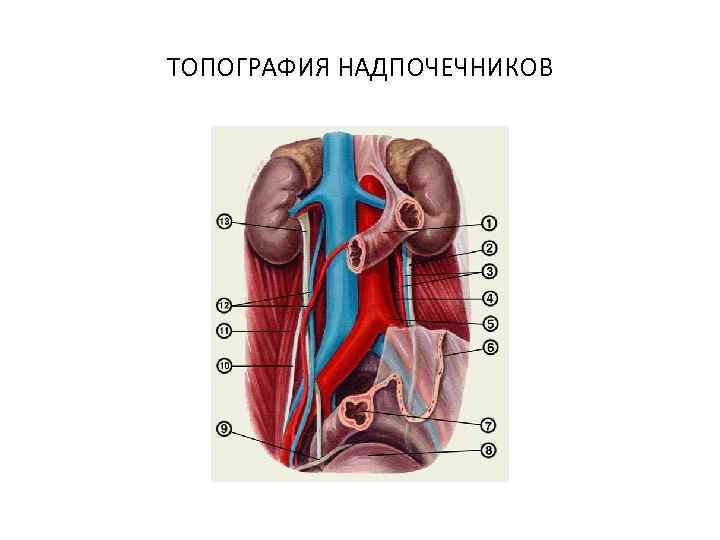

ТОПОГРАФИЯ НАДПОЧЕЧНИКОВ

ТОПОГРАФИЯ НАДПОЧЕЧНИКОВ